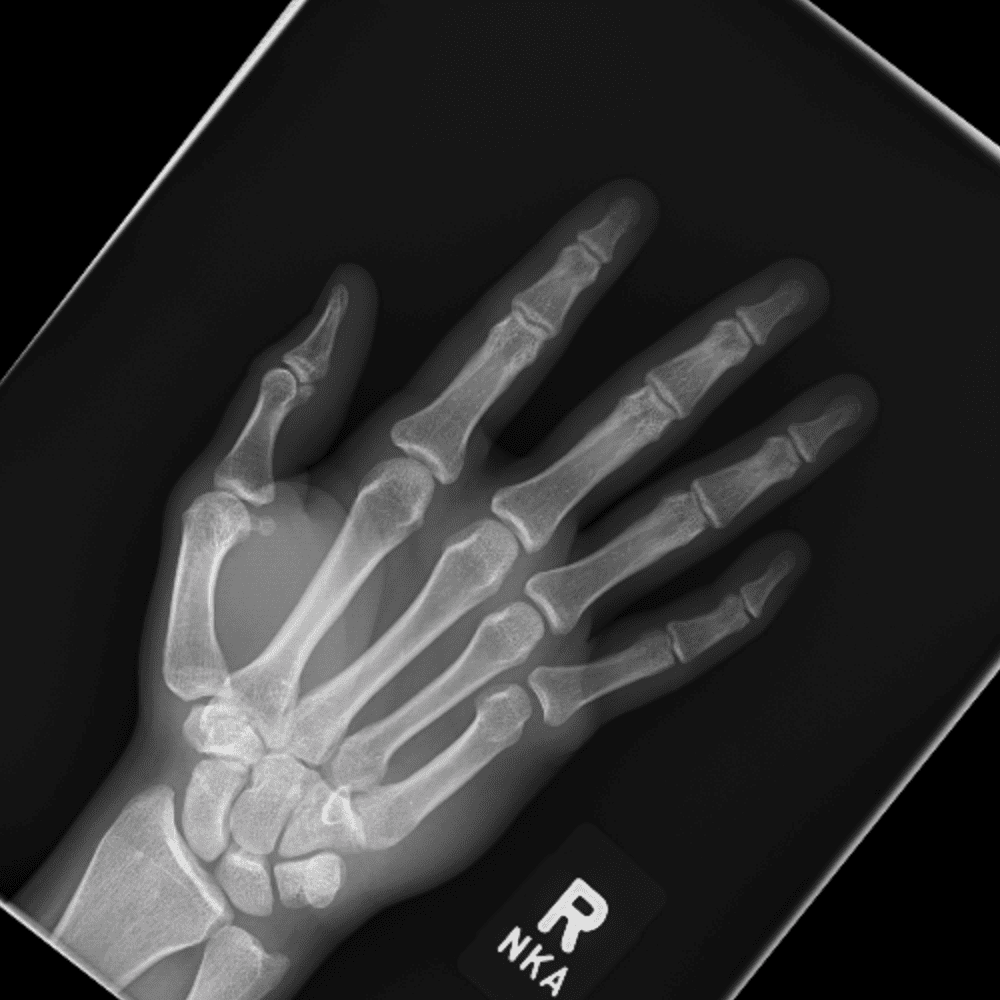

Simuliert den Dienst durch subtile oder schwierige Fälle und einige Normalbefunde.

30 Fälle